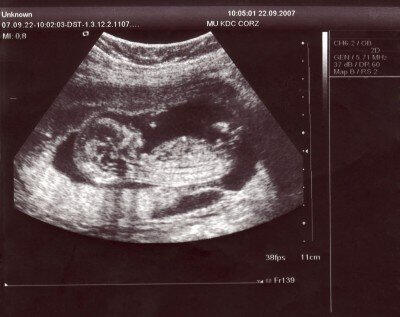

Těhotenství je jedním z nejvýznamnějších a nejkrásnějších období života ženy. Začíná oplozením vajíčka spermií a končí porodem, přičemž jeho délka činí přibližně 270 dní, počítáno od prvního dne poslední menstruace. Příznaky těhotenství jsou různé a mohou zahrnovat vynechání menstruace, nevolnost, zvracení, časté močení, citlivost prsou či zvýšenou podrážděnost.Diagnózu těhotenství mohou ženy zpočátku provést samy pomocí komerčně dostupných testů. Tyto testy však nemusejí být vždy spolehlivé, proto je vhodné vyhledat gynekologa. Lékař těhotenství potvrdí krevním vyšetřením na hCG (choriový gonadotropin) nebo ultrazvukem. Na začátku těhotenství se provádí vaginální ultrazvuk, v pozdějších týdnech pak transabdominální (přes břišní stěnu).Po potvrzení živého těhotenství obdrží budoucí maminka těhotenskou průkazku, kde jsou zaznamenány veškeré údaje o průběhu těhotenství a zdravotním stavu matky. Průkazku je vhodné mít vždy u sebe.

Pravidelná vyšetření• Sběr subjektivních údajů a stesků těhotné• Zevní vyšetření, měření hmotnosti a krevního tlaku• Chemické vyšetření moči• Poševní vyšetření• Od 24. týdne sledování srdečních ozv ploduNepravidelná vyšetřeníPrvní ultrazvuk (7.–12. týden)• Určení stáří těhotenství a data porodu• Kontrola počtu plodů a jejich základního vývoje• Zobrazení tlukoucího srdíčka plodu• Možnost získání první fotografie miminka16. týden• Stanovení krevní skupiny a Rh faktoru• Vyšetření titru erytrocytárních protilátek• Krevní obraz a serologické testy (např. protilátky proti syfilis)• Biochemický screening vrozených vad ve II. trimestru• Kontrola moče (střední proud)• Důležitá je znalost Rh faktoru rodiček s Rh-negativní krví18.–22. týden• Ultrazvukový screening plodu zaměřený na vrozené vady• Možnost určení pohlaví dítěte24.–28. týden• Screening poruchy glukózové tolerance30.–32. týden• Kontrola titru erytrocytárních protilátek u Rh-negativních žen• Krevní obraz, serologické vyšetření HBsAg a HIV• Druhý ultrazvukový screening: růst, poloha, velikost dítěte, poloha placenty36.–37. týden• Výtěr z pochvy na přítomnost streptokoků skupiny B• Kardiotokografické (KTG) vyšetření – sledování srdeční činnosti plodu a děložních kontrakcí• Od 38. týdne se KTG provádí pravidelně

Integrovaný screening

Ultrazvuk není pojišťovnou hrazen při každé těhotenské kontrole.

Za fysiologickou graviditu hradí UZ pojišťovna pouze třikrát. Lze však miminko vidět pokaždé za přímou úhradu, viz. ceník.Chcete-li Vaše miminko vidět na ultrazvuku při každé plánované kontrole, doporučuji "Těhotenský balíček"

| Fotografie plodu z UZ + zaslání do e-mailu | 100 Kč |

| Těhotenský balíček ** | |

| (UZ při každé kontrole, určení pohlaví, 2x foto, přítomnost blízké osoby u UZ vyšetření) | 2000 Kč |

| UZ vyšetření po 36. týdnu | |

| Těhotenský balíček obsahuje nadstandartní, pojišťovnou neplacené ultrazvukové vyšetření při každé kontrole, určení pohlaví plodu, bude-li to spolehlivě možné a 2 fotografie při každé návštěvě (bude-li plod spolupracovat). Při vyšetření je možná přítomnost doprovodu (např. partnera). Vyšetření je zaměřeno jen na změření velikosti plodu, polohy plodu, kontrola akce srdeční ( není zaměřeno na vyhledávání vrozených vývojových vad, které se zjišťují mezi 20.- 22. týdnem gravidity). |